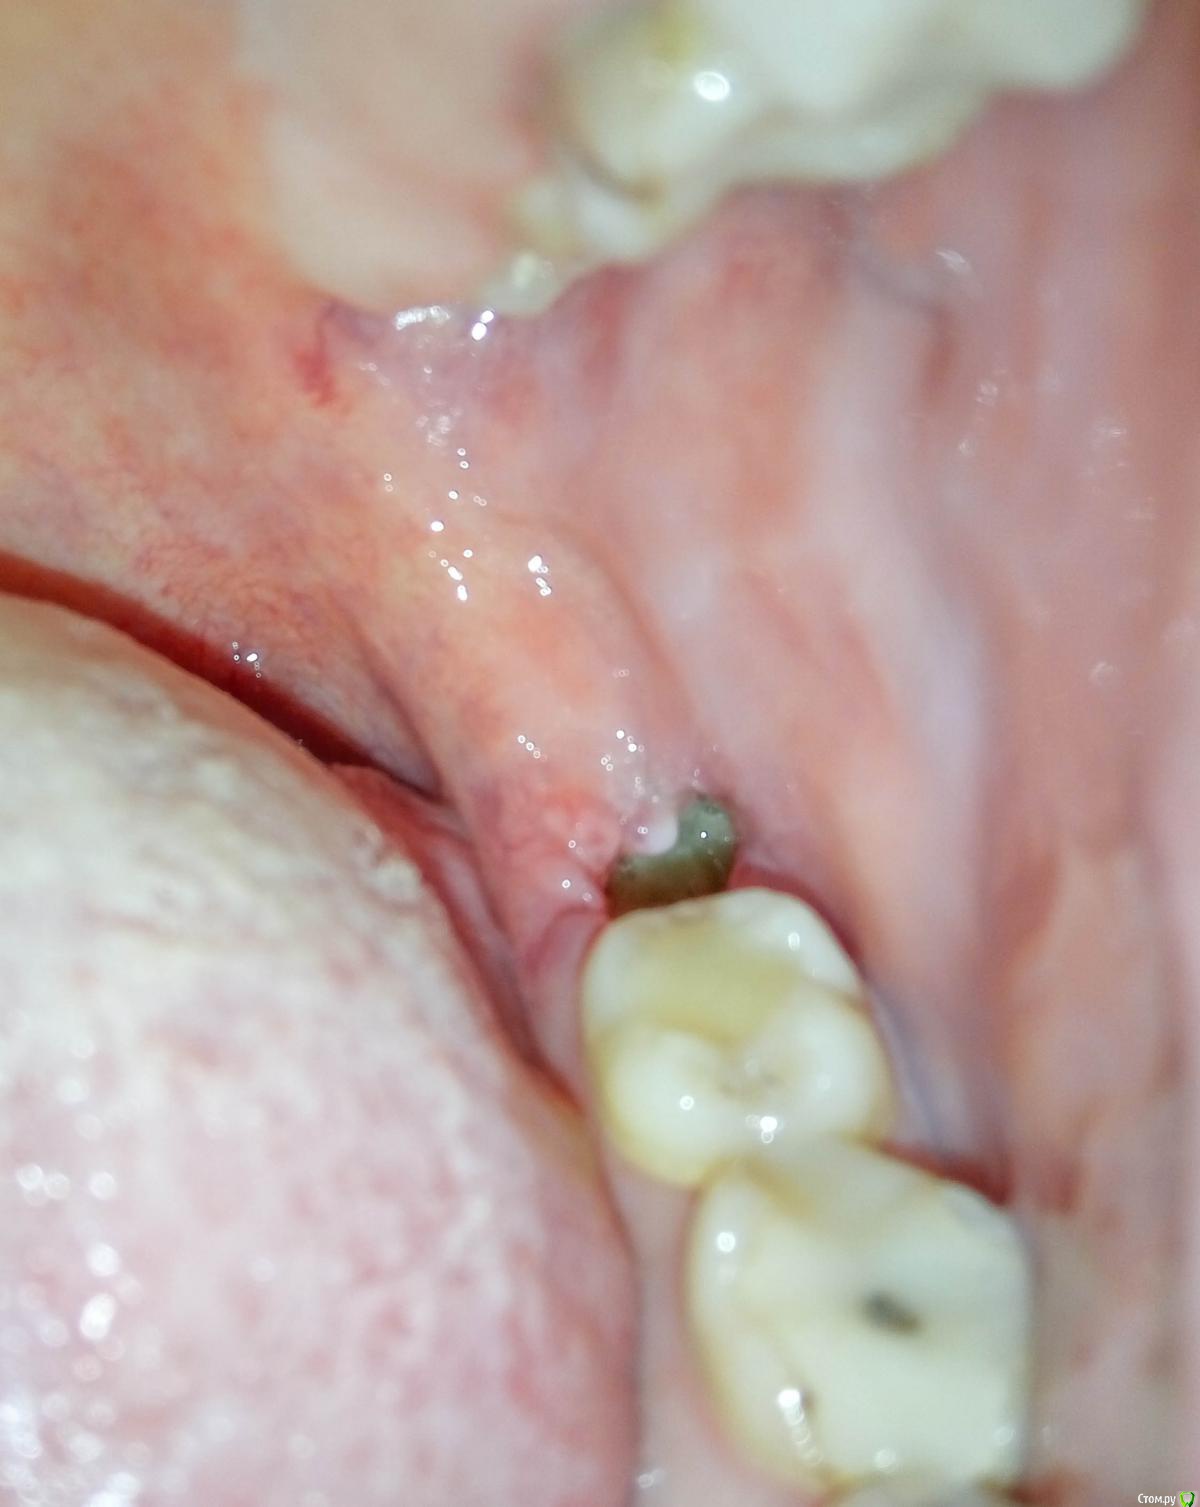

Ника9115 Опубликовано 1 марта, 2017 Поделиться Опубликовано 1 марта, 2017 (изменено) Здравствуйте, очень волнуюсь из за лунки, удаление было 14 февраля, сложное, более часа, лунка была заложена лекарством, сгустка не получилось, 2 недели ходила меняли губки + пытались 2 раза накладывать швы, один раз они сами рассосались на следующий день, а второй раз наложили которые надо снимать через неделю, так на след день они тоже разошлись, поэтому ложили постоянно губки, так как они выпадали постоянно, в то воскресенье положили последнюю и сказали больше не надо, всё так затянется, присутствую ноющие, иногда тянущие боли, не сильные, но не приятные, врач сказал, что лунка большая и болеть будет долго, вчера заметила внутри лунки какое-то уплотнение, со стороны языка, испугалась, пошла к врачу, он просто посмотрел , не трогал не чего, сказал всё нормально и отправил домой, сказал это лунка так стягивается, но что то мне подсказывает, что это не так, я все ровно переживаю... Живем в маленьком городе и больше обратиться некуда. Сказал если будут нестерпимые боли , то приходить. Фото прилагаю , первое и второе фото как вчера и сегодня , а последнее как было 22 февраля, прям как шишечка появилась. Изменено 1 марта, 2017 пользователем Ника9115 1 1 Ссылка на комментарий

Ника9115 Опубликовано 4 марта, 2017 Автор Поделиться Опубликовано 4 марта, 2017 Здравствуйте еще раз , удалили 14 февраля, то есть прошло почти 3 недели , десна немного ноет, и красная , при дотрагиваться языком немого больно, на фото выше видно лунку, там фибрин как я поняла, сегодня посмотрела в лунку, а там нету этого налета белого больше , шишечка та прошла помойму. Вот как выглядит лунка сейчас, боюсь воспаления опять , но вроде становится меньше, беспокоит десна, о что она красноватая и болит при дотрагивание. Ссылка на комментарий